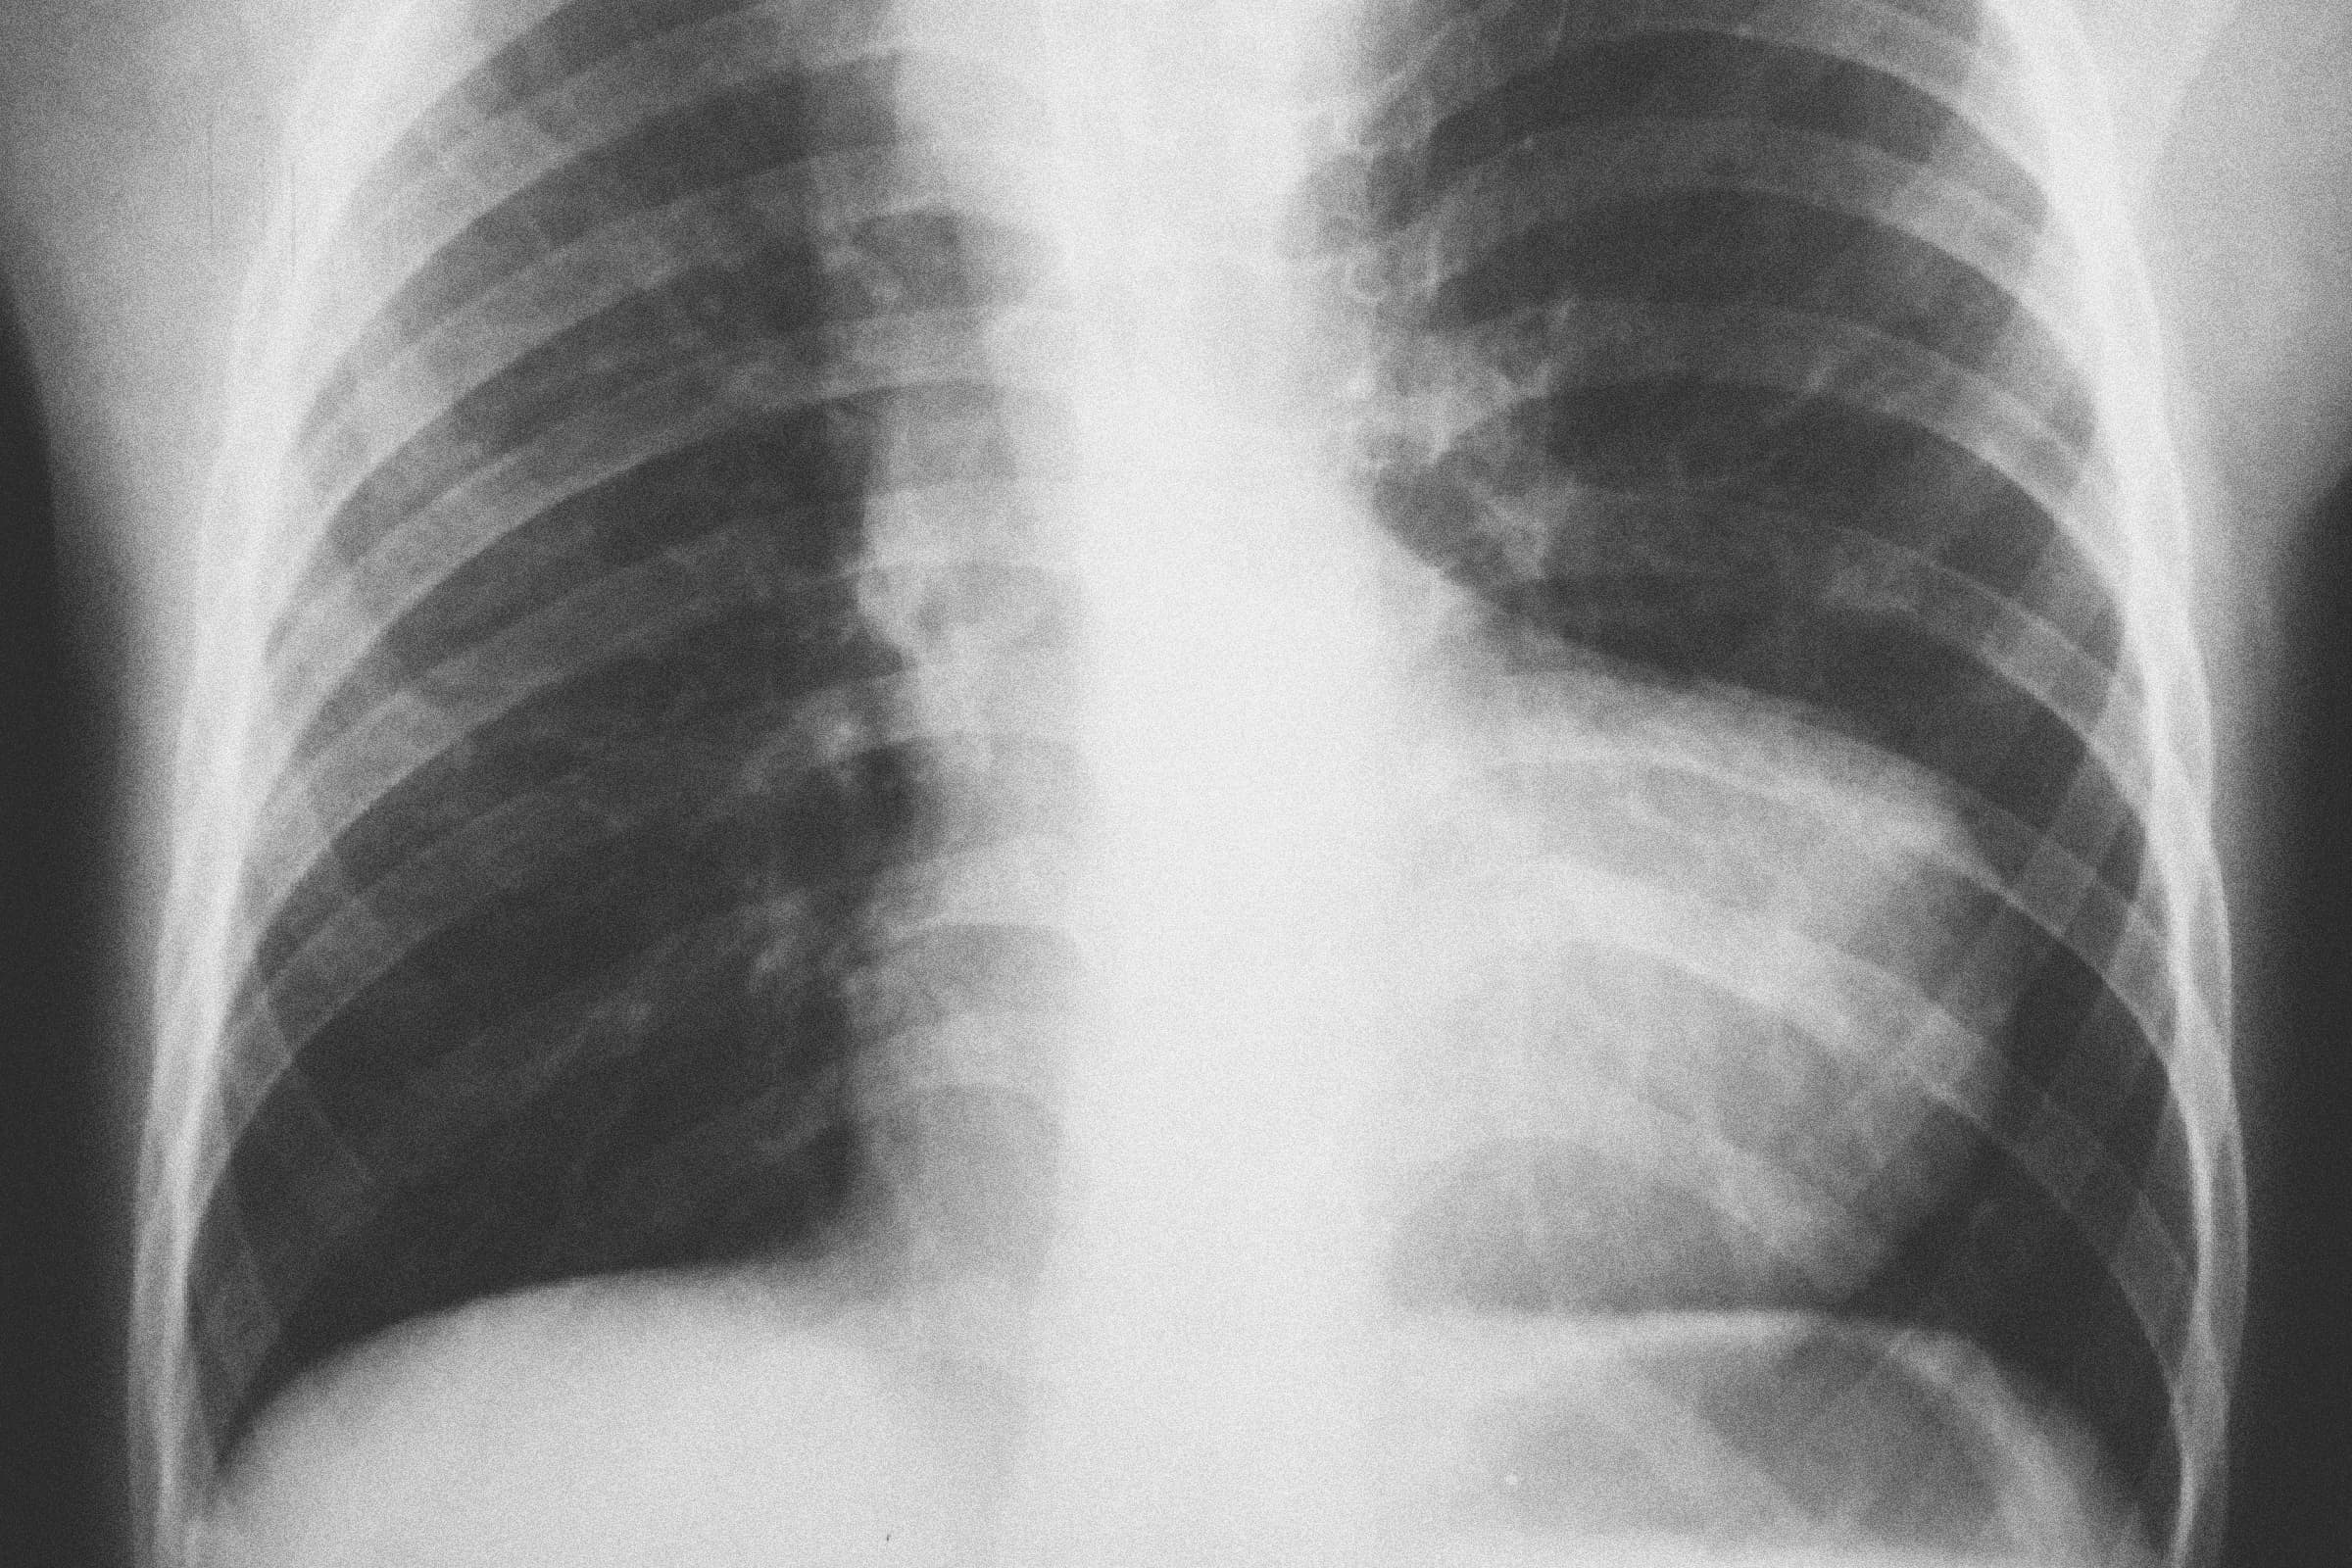

Myint was born with two heart defects—tetralogy of Fallot and dextrocardia. His heart was positioned incorrectly and weakened by an abnormal aorta, a hole between its chambers, and an obstructed connection to his lungs.

At the Mae Tao Clinic, Myint received the official diagnosis he had been seeking for years. His combination of cardiac defects was causing oxygen-poor blood to flow out of his heart and into the rest of his body. In the United States, surgery to treat his heart conditions is typically performed in the first year of life—Myint had lived with these heart defects for 14 years.